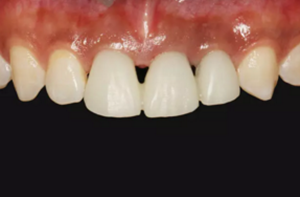

圖2 術(shù)前口內(nèi)像

圖14 術(shù)后4個月口內(nèi)像

圖23 最終修復(fù)后即刻口內(nèi)像

圖25 最終修復(fù)后復(fù)查口內(nèi)像